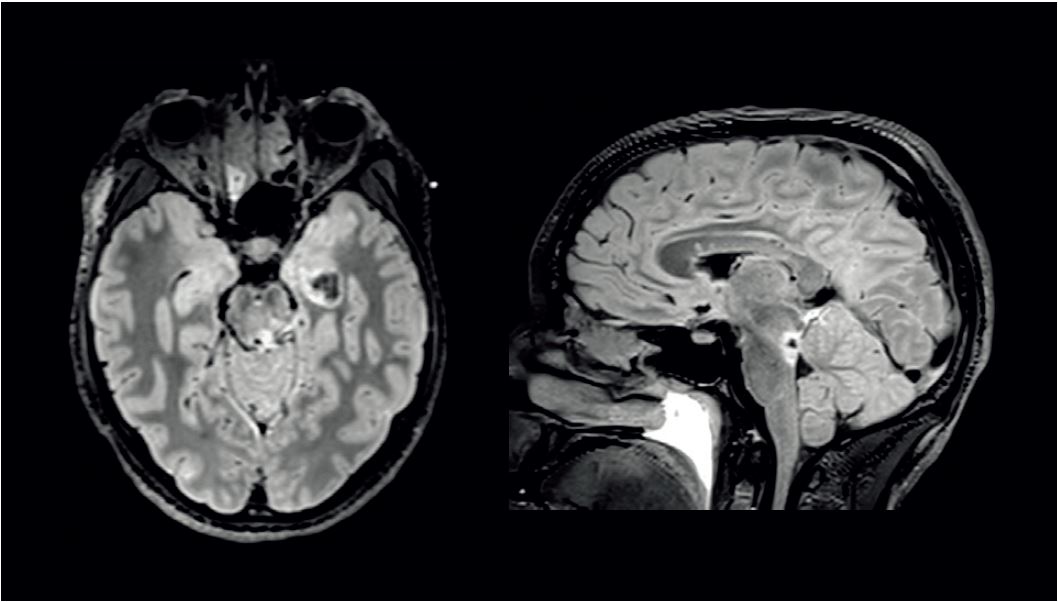

FLAIR МРТ-зображення, реконструйовані в аксіальній і сагітальній площинах (рис. 1), показали церебральний геморагічний забій мосту, що є поширеним явищем при значній травмі голови.

Церебральний геморагічний забій був виявлений поблизу лівого кірково-спинномозкового відділу, який служить основним каналом передачі інформації між вищими корковими структурами, скелетними м’язами, а також спинно-таламічними шляхами, одним із найважливіших сенсорних шляхів нервової системи. На знімку чітко видно «дзеркальний» внутрішній геморагічний струс мозку зліва.

Рис. 1. FLAIR зображення, реконструйовані в аксіальній і сагітальній площинах